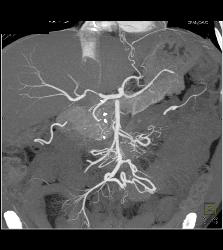

Carcinoid Tumor Encases the PV/SMV With Cavernous Transformation of the Portal Vein (CTPV)